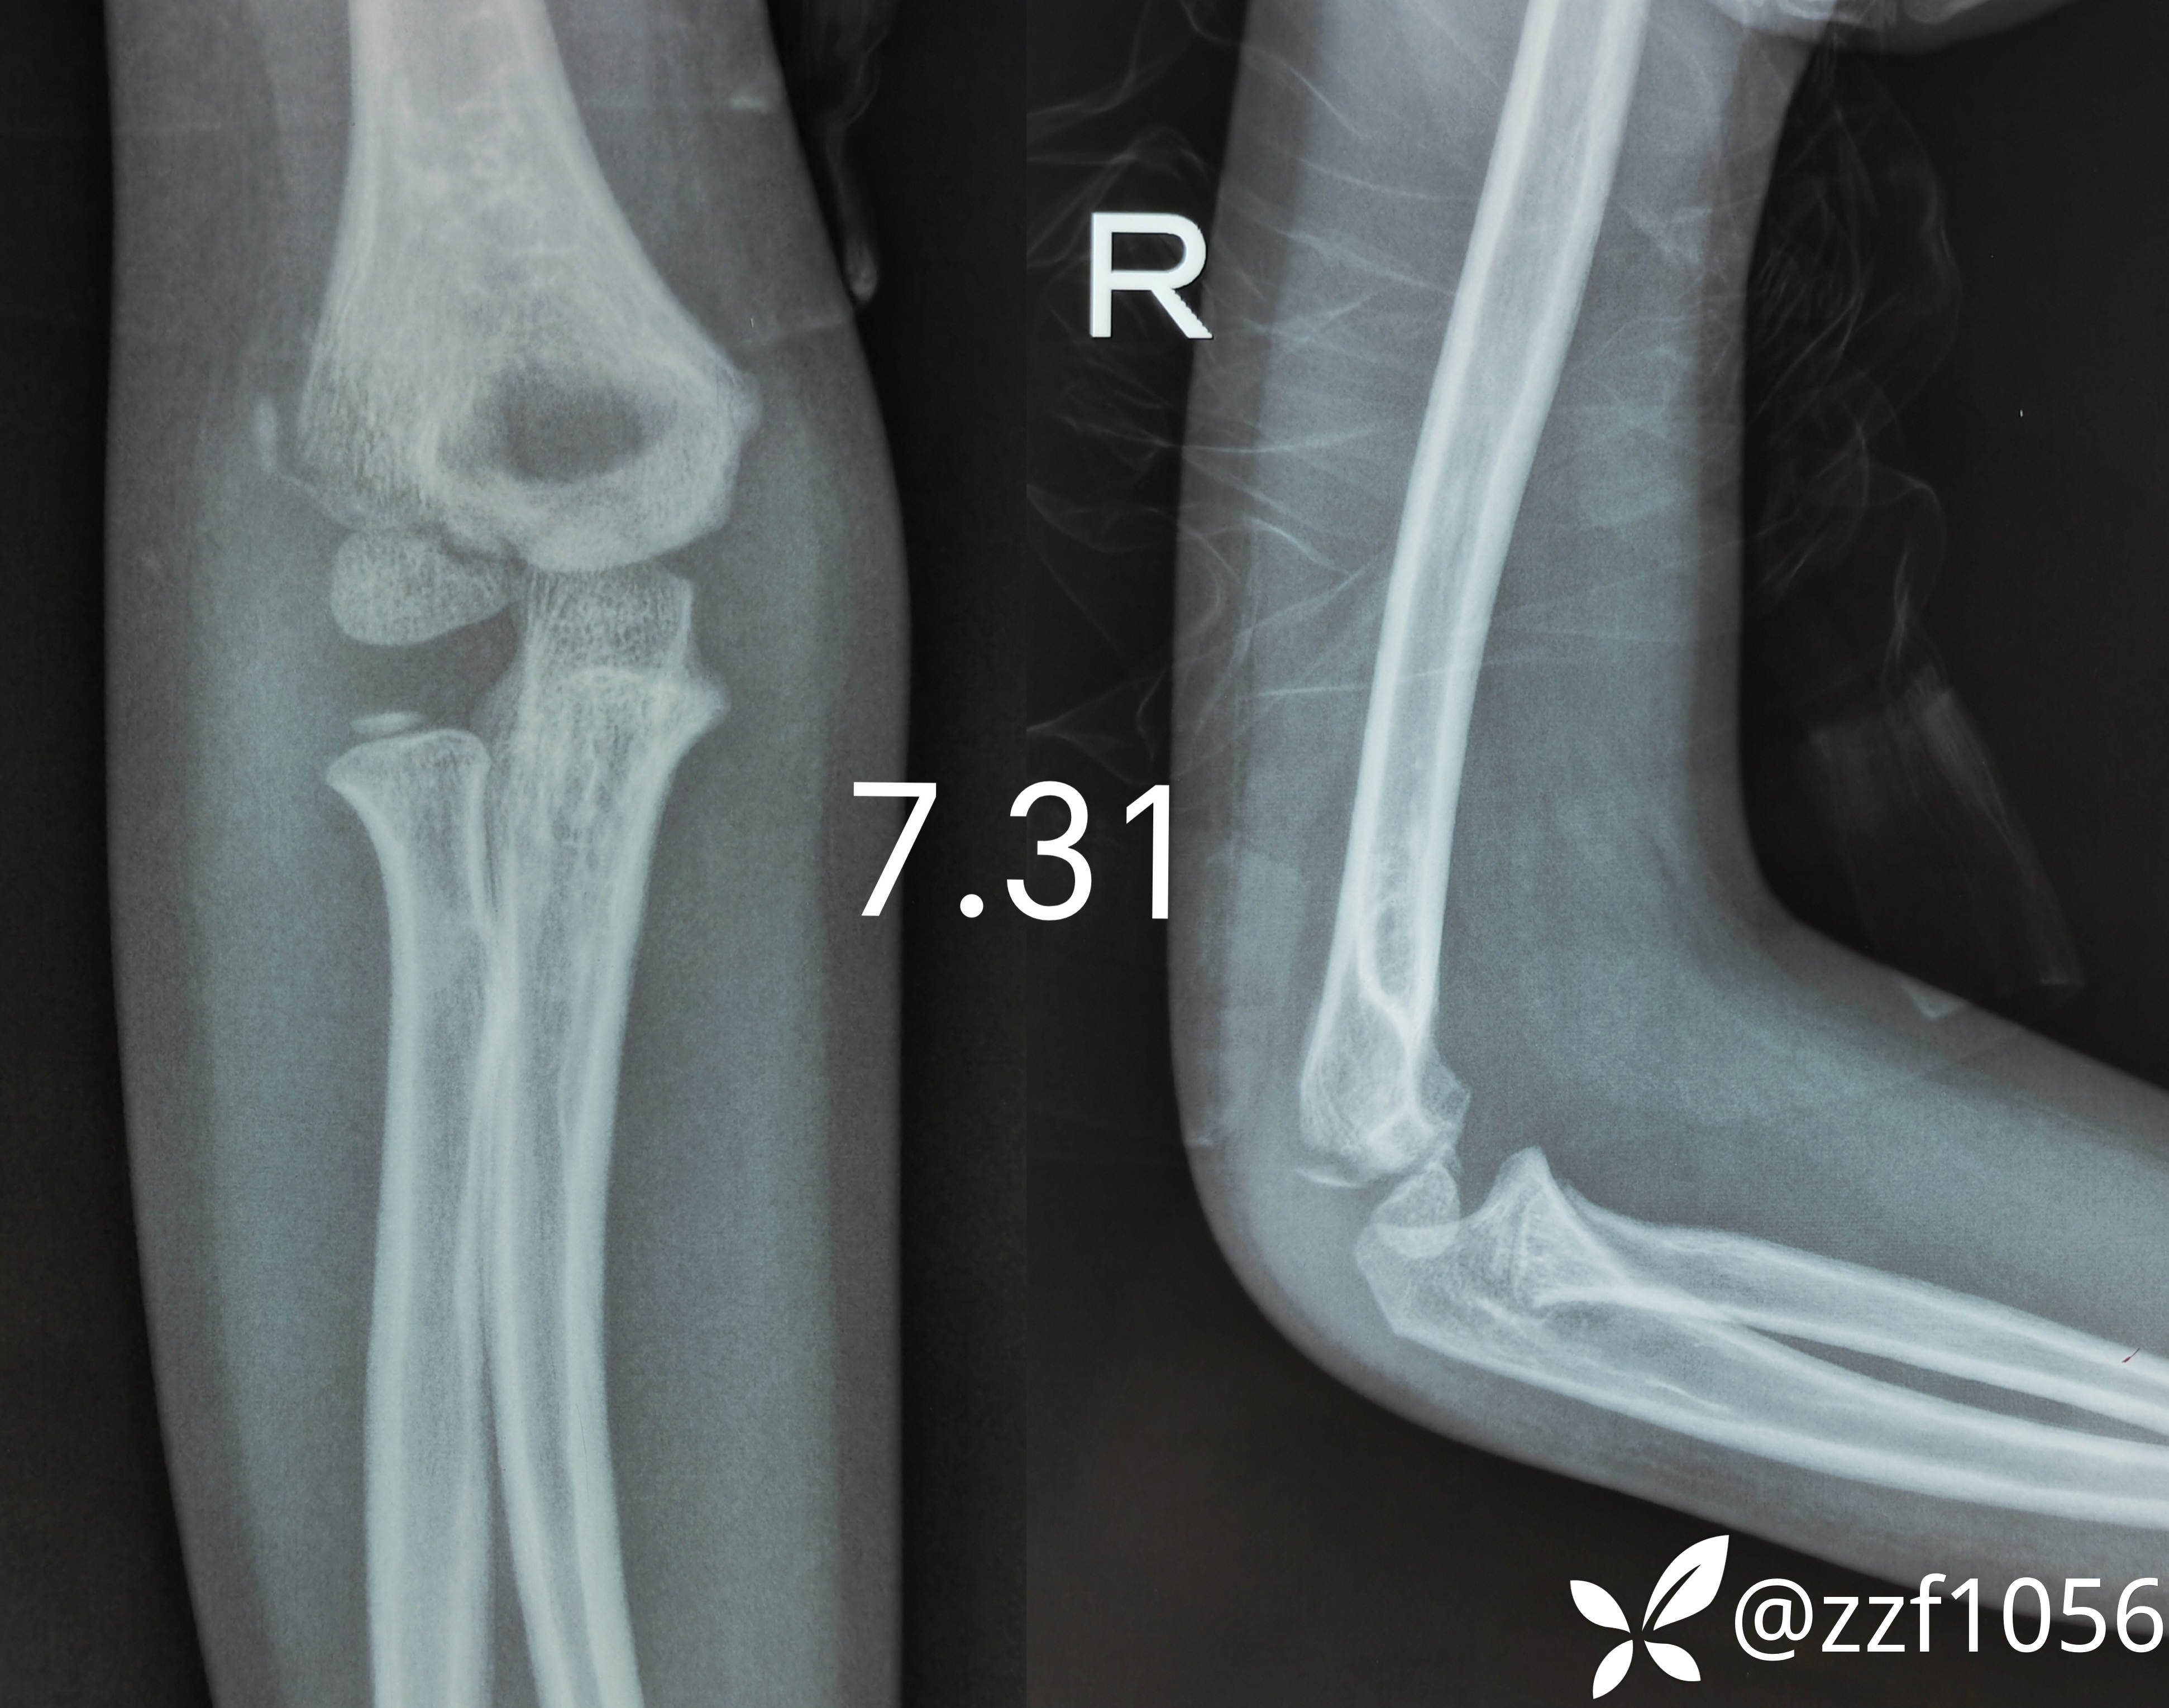

当时门诊大夫打了个石膏保守治疗

保守半月昨日再次来我院就诊,门诊摄片显示